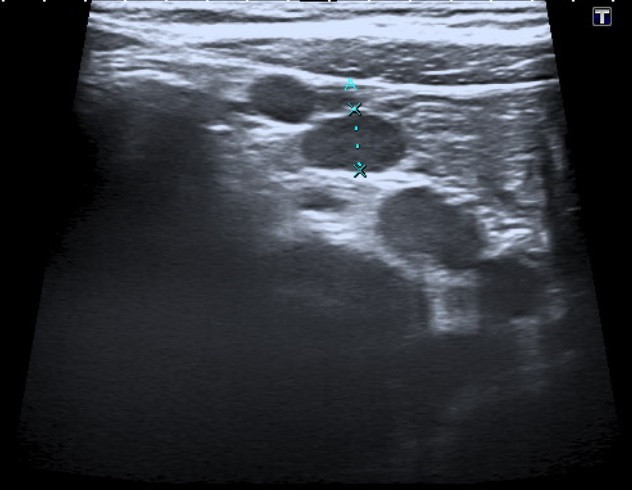

• Ecografía abdominal.